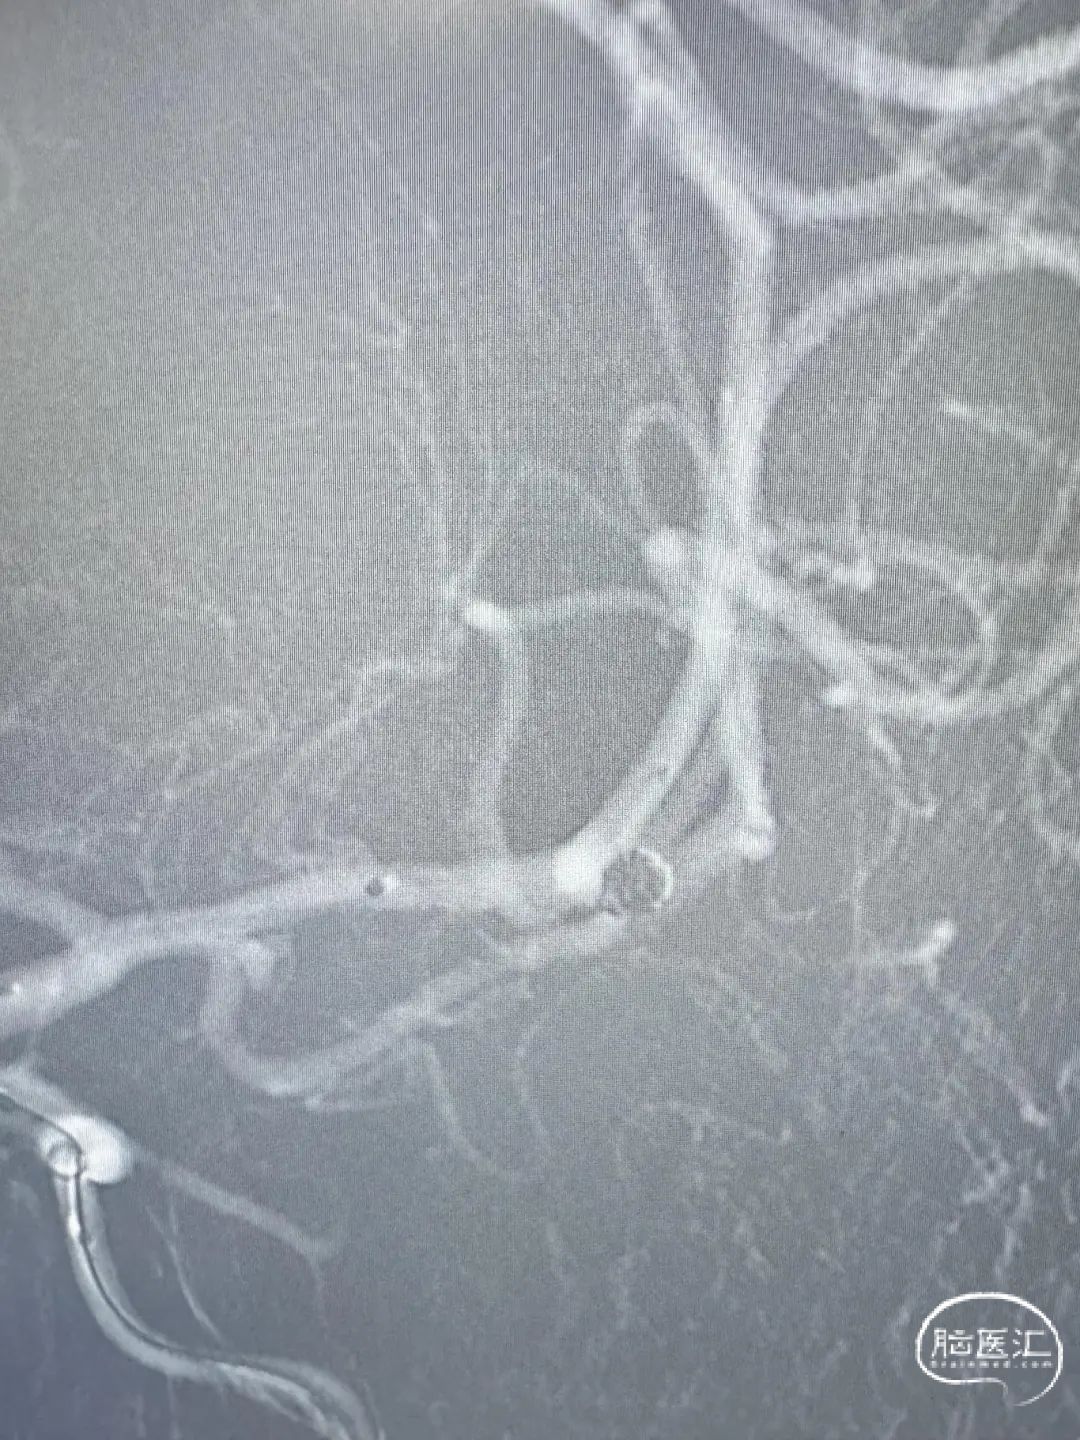

急诊头颅CTA:左侧大脑中动脉M1远端分叉处动脉瘤,左侧大脑中动脉M1段颞干分叉处动脉瘤。

左侧大脑中动脉M1段颞干分叉处动脉瘤

左侧大脑中动脉M1远端分叉处动脉瘤

术后正侧位造影。

动脉瘤完美栓塞,一个支架,两根微导管,一根微导丝主导全程,填塞致密。